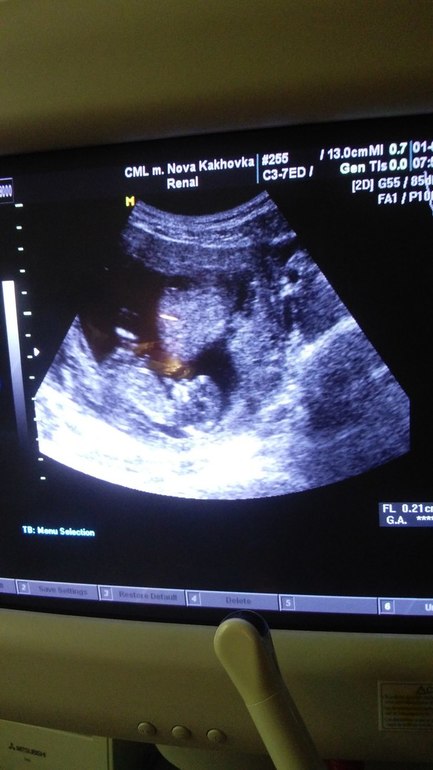

Вопросы про УЗИ, обследования и анализы: что, где, как, когда?Показала фото с УЗИ мужу - сказал что это 100% мальчик (сам хочет девочку), открыла ему фото УЗИ других мамочек, на страничках которых уже указан пол - назвал все верно! По лобной кости судит... Любопытство мое меня съедает:):):) Интересно ваше мнение по этому поводу)))

Да, на фото 12 с половиной недель:)